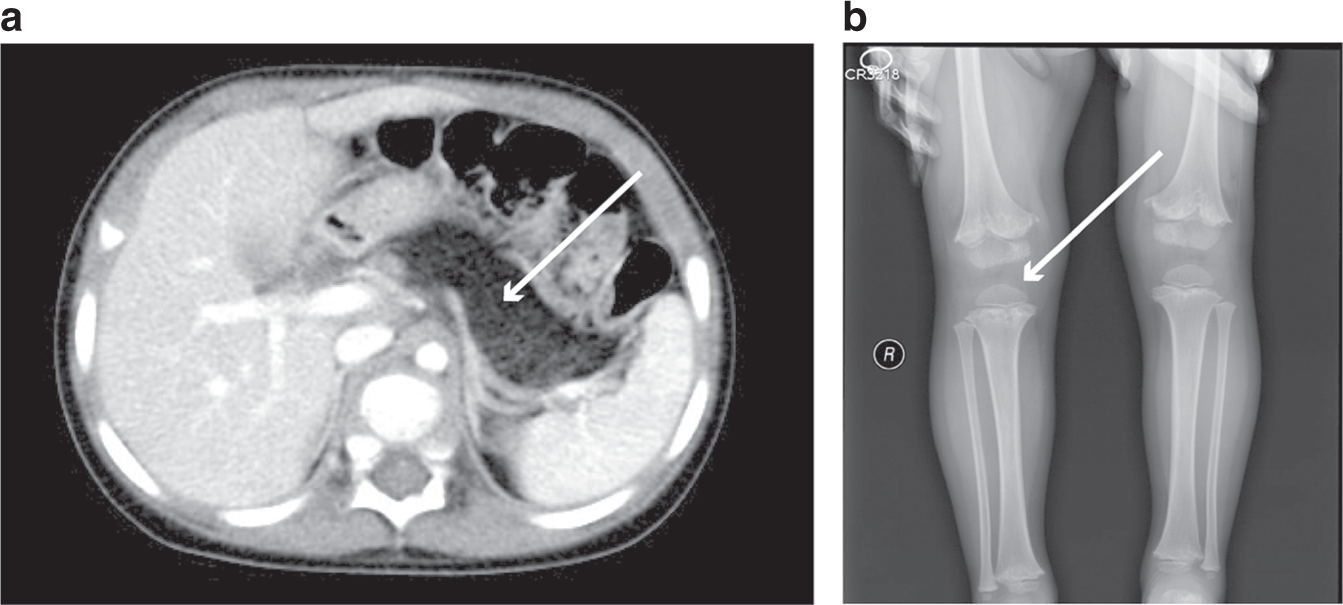

Radiologic findings of patients with fatty diarrhea. (a) Enhanced computed tomography (CT) of the abdomen shows pancreatic lipomatosis in patient 89. (b) A lower limb plain film shows metaphyseal dysplasia in patient 89.